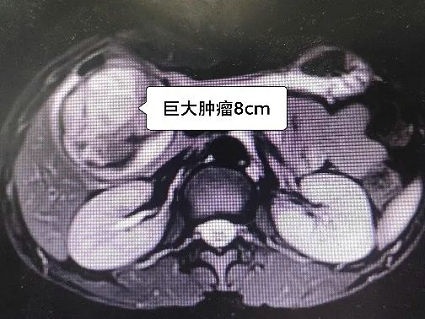

陈升阳主治医师接诊并详细询问病史后,安排增强CT及MRI等术前评估检查。检查结果提示胰腺实性假乳头状瘤可能性大(一种预后较好的胰腺肿瘤)。

由于肿瘤巨大,局部胆管、胰管推挤明显,肿瘤周边比邻关系复杂,经过精心的术前准备,李晓勇教授带领团队制定了合理的手术方案:腹腔镜下胰腺肿瘤切除术,若术中肿瘤侵犯比邻胆管或胰管,再改行胆肠吻合手术或胰十二指肠切除手术。玲玲父母对李晓勇教授及陈升阳主治医师耐心地讲解病情和手术方案十分感激,抱着信任的态度在手术同意书上签了字。